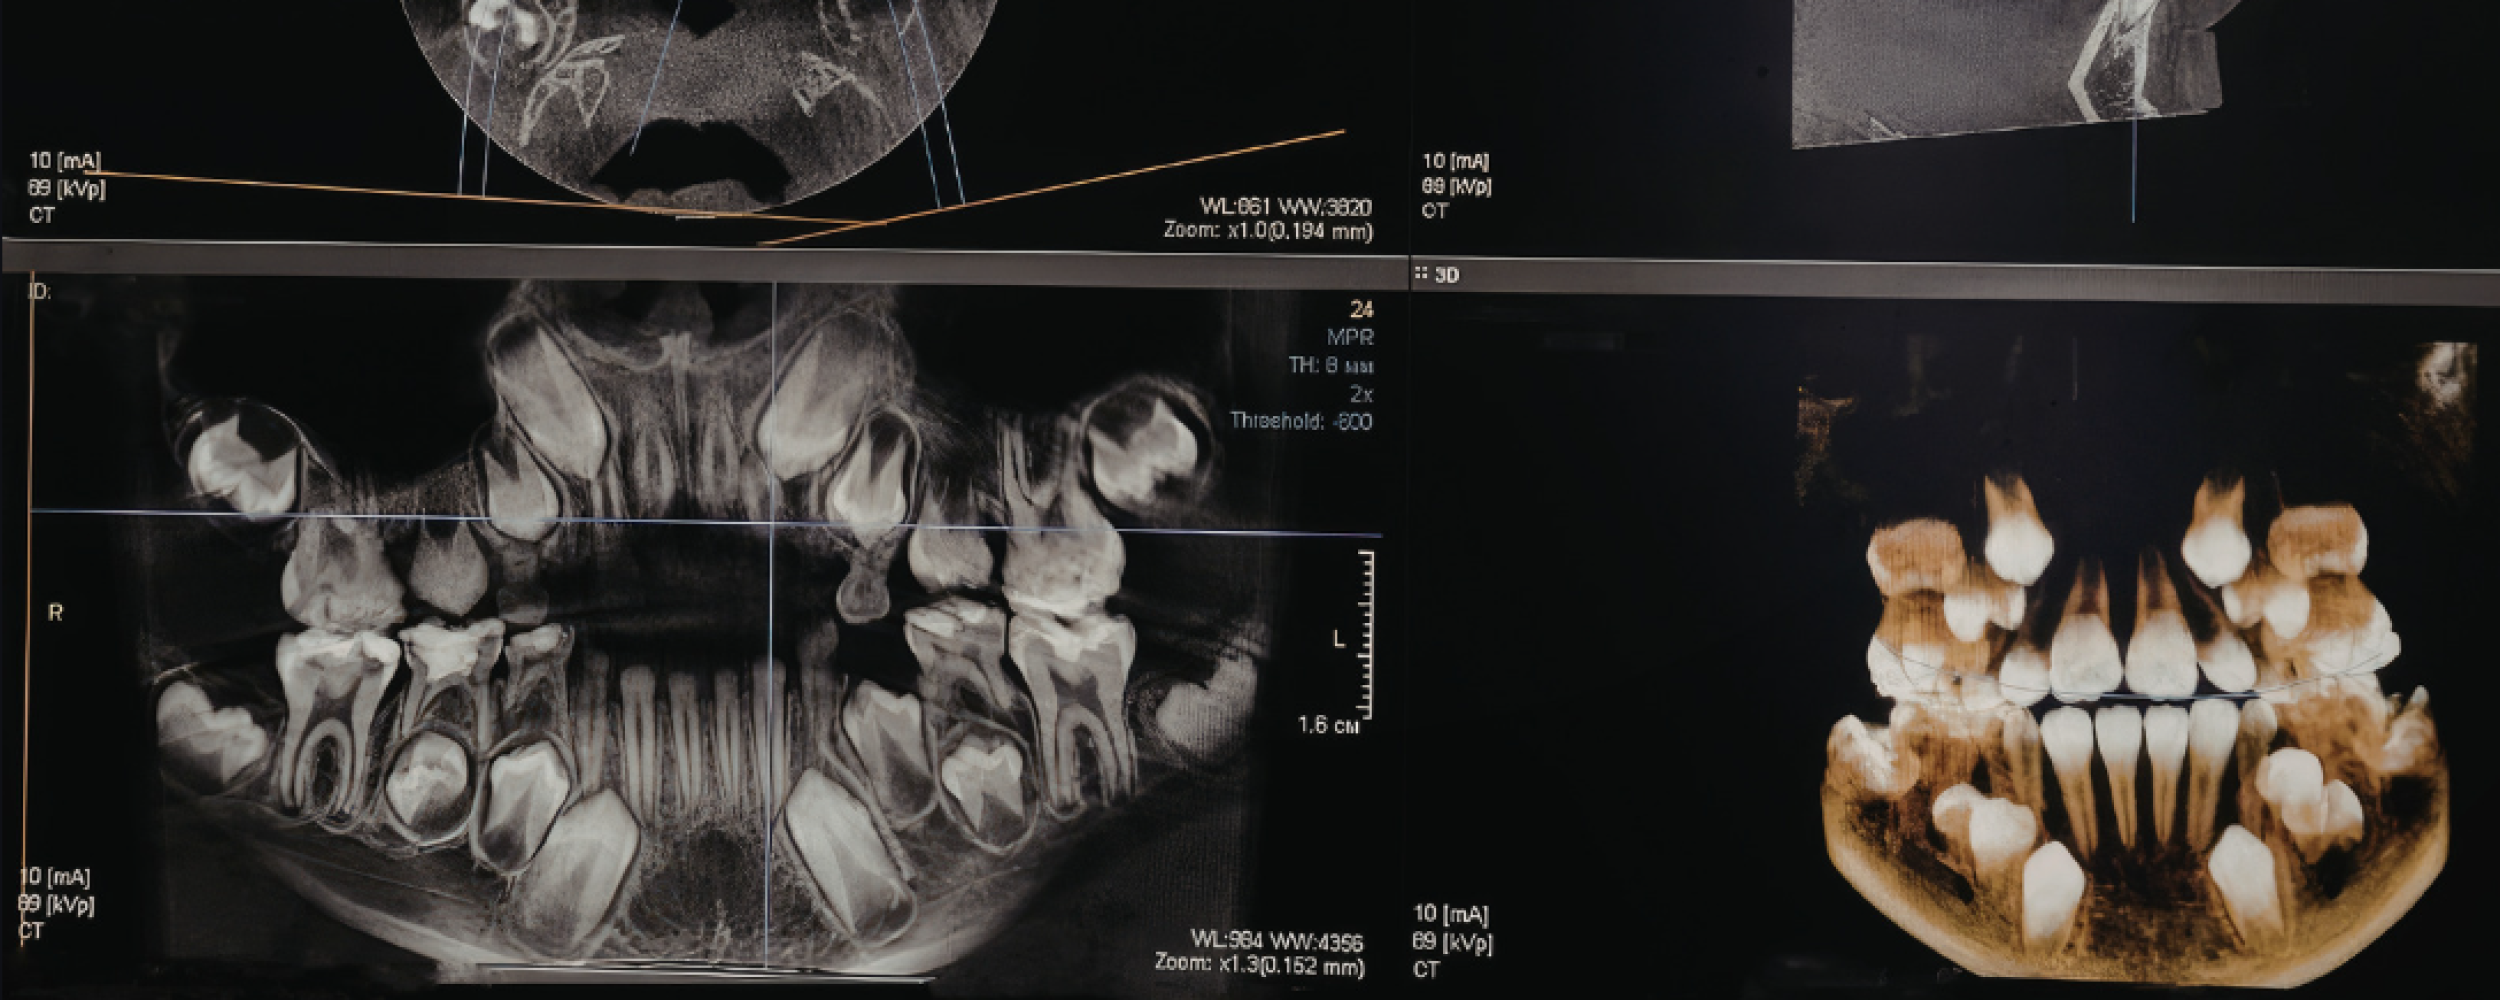

At Shenstone Dental Centre, we use advanced CBCT scanning to plan treatments with a high level of accuracy, particularly for dental implants. This means we can plan your treatment with confidence and avoid unnecessary surprises

A CBCT scan is a detailed 3D scan of your teeth, jaw, and surrounding structures. It allows us to see bone levels, nerve positions, and facial anatomy far more clearly than standard X-rays.

This allows us to plan your treatment with a level of precision that simply isn’t possible with standard X-rays.

CBCT allows us to plan your treatment with confidence. By seeing everything in 3D, we can assess your jaw and surrounding structures in far greater detail.

• Accurately assess bone quality and volume

• Identify important areas such as nerves and sinuses

• Plan implant placement with precision

• Reduce risks and improve long-term results

CBCT scans are safe, non-invasive, and use a low level of radiation, significantly lower than traditional CT scans.

The scan itself is quick, simple, and completely painless. The scanner gently rotates around your head for a few seconds, capturing a full 3D image.